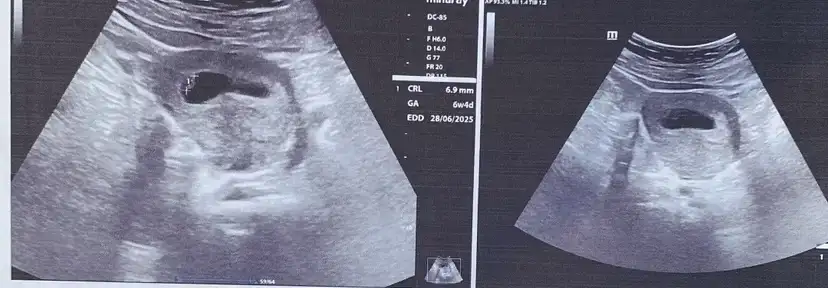

Kızlar aranızda keseden cinsiyet tahmini yapabilen var mı yarın 10 hafta olacak inanılmaz merak ediyorum bi baksanız 😘

Eklentiler

• IMG_5583.webp

IMG_5583.webp

23,1 KB · Görüntüleme: 142